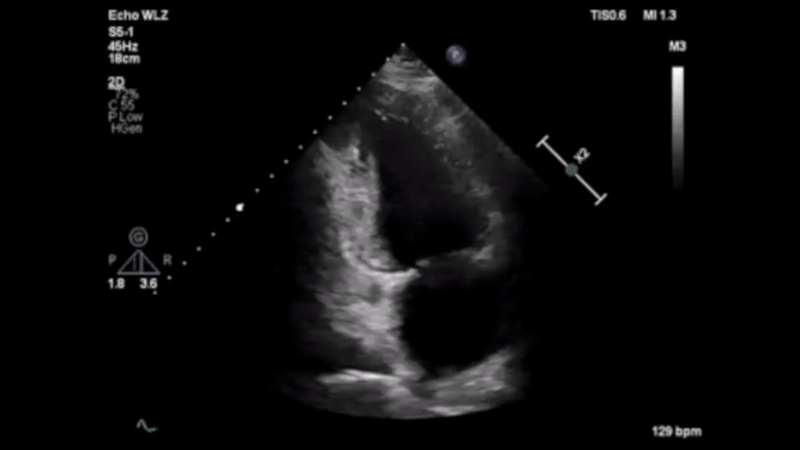

Leveraging advanced analytics and AI, our non-invasive solutions empower clinicians with immediate, data-driven insights - minimizing risks and improving patient outcomes.

By integrating seamlessly into ICU, emergency, and perioperative workflows, we enable faster interventions and more precise decision-making when every second counts.

Guided by a vision of data-driven healthcare, we aim to expand beyond cardiac imaging, forging new possibilities in medical AI and unlocking meaningful collaborations that elevate patient care worldwide.